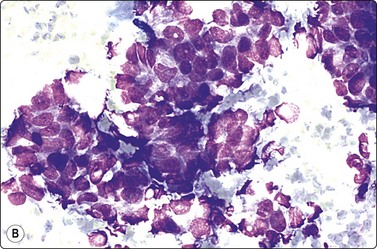

image image

Fig. 7.2 Non-neoplastic glandular breast tissue and low-grade duct carcinoma

Low-power view; (A) Bimodal population of epithelial sheets and single bipolar nuclei of non-neoplastic glandular breast tissue; (B) Single population of epithelial cells in low-grade carcinoma (MGG, LP).

Fig. 7.3 Non-neoplastic glandular breast tissue and low-grade duct carcinoma

High-power view, air-dried smears; (A) Non-neoplastic glandular breast tissue; (B) Low-grade duct carcinoma. Note single bipolar nuclei in A, and absence of bipolar nuclei, relatively mild nuclear atypia and some loss of cohesion of malignant cells in B (MGG, HP).

Fig. 7.4 Non-neoplastic glandular breast tissue and low-grade duct carcinoma

High-power view, Pap-stained smears; (A) Bimodal population in smear from non-neoplastic breast; (B) Single and clustered cells in low-grade carcinoma; some single cells probably stromal (Pap, HP).